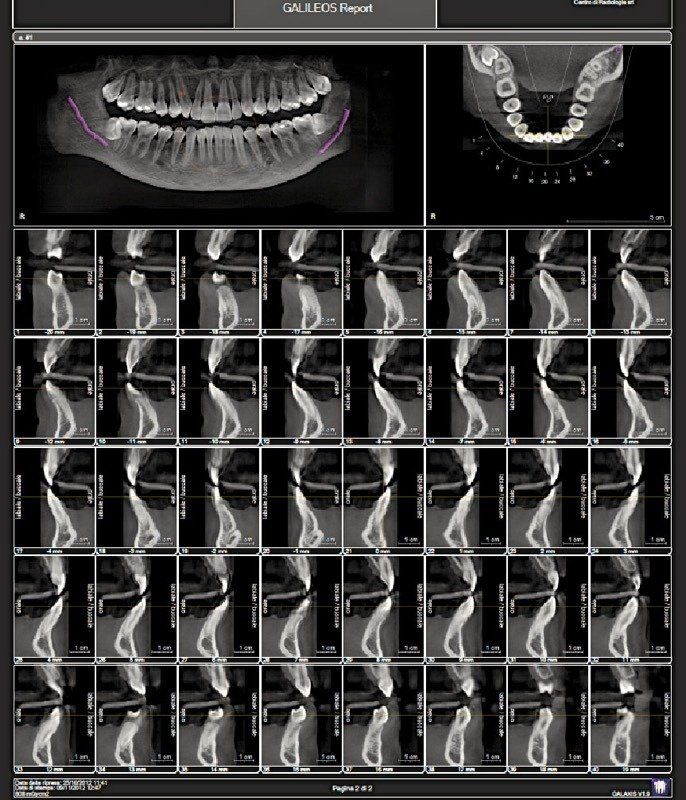

Il Centro di Radiologia Muglia - Rago - Scaletta è dotato di un'apparecchiatura di ultima generazione, il Dentascan Cone Beam 3D, con cui vengono eseguiti:

- ortopantomografie digitali dirette OPT - panoramica dentale;

- esami in 3D delle arcate dentarie;

- studi pre e post implantari;

L’esame consente al dentista una visualizzazione anatomica totale delle arcate dentarie e delle strutture del distretto maxillo-facciale nei vari piani ortogonali.